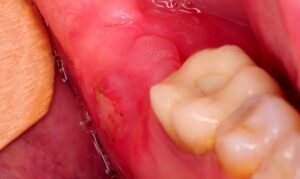

3.4 Gum Flap (Pericoronitis) Around Wisdom Teeth

A partially erupted tooth may have gum tissue covering it, which can become infected or swollen. This area easily traps food and bacteria, causing persistent pain and unpleasant odor. Gum flaps are especially common with lower wisdom teeth and often require surgical removal or other treatments.